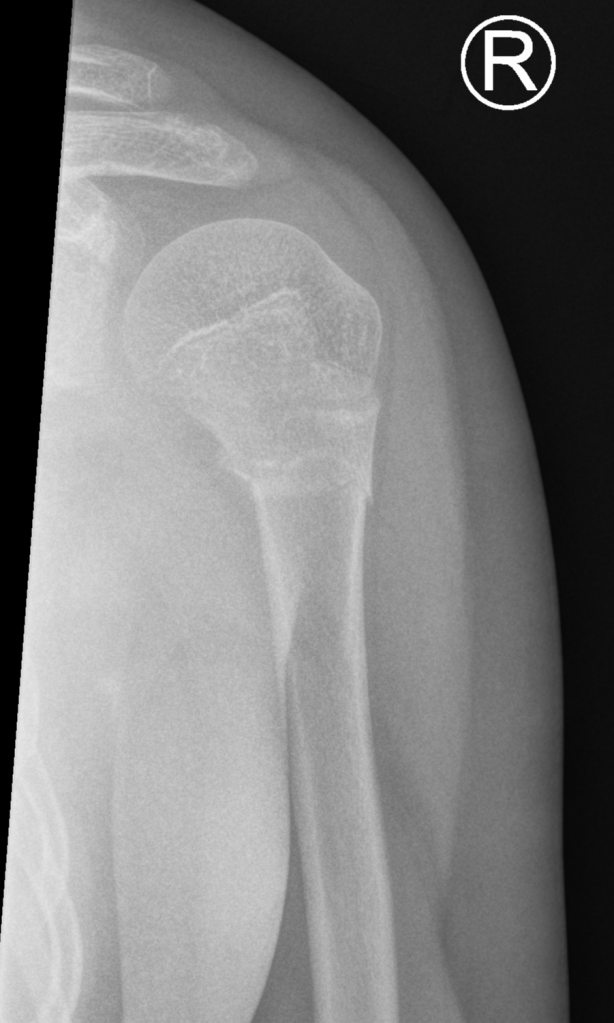

Frontal and lateral views of minimally angulated incomplete (greenstick) fracture through the proximal metaphysis. No extension to the physis. Normal glenohumeral alignment.